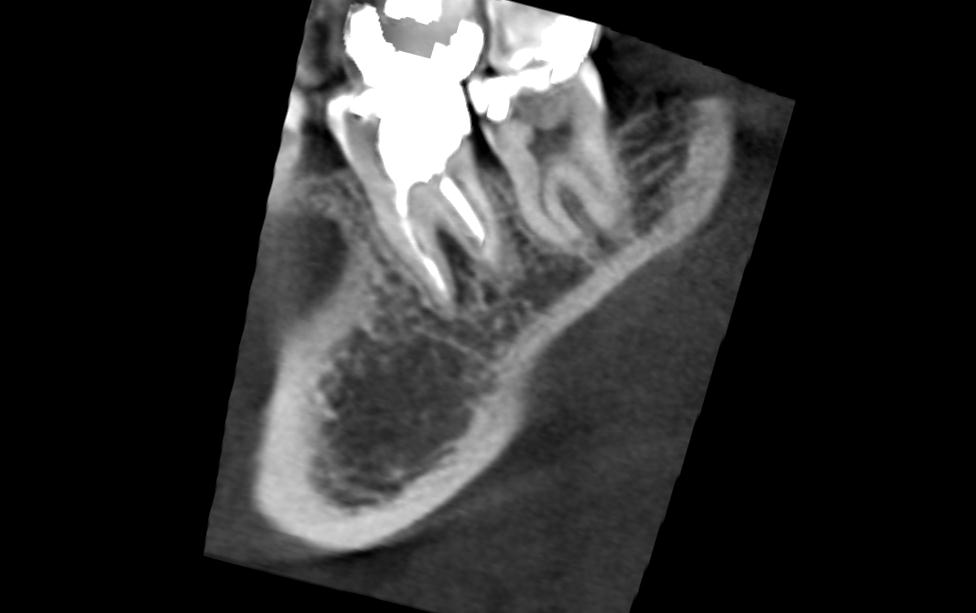

А вот такие снимки чтото скажут:Нажмите на изображение для увеличения

Название: Image2.jpg

Просмотров: 72

Размер:	30.8 Кб

ID:	4314303Нажмите на изображение для увеличения

Название: Image4.jpg

Размер:	32.0 Кб

ID:	4314304Нажмите на изображение для увеличения

Название: Image1.jpg

Просмотров: 73

Размер:	14.4 Кб

ID:	4314305Нажмите на изображение для увеличения

Название: Image5.jpg

Просмотров: 62

ID:	4314306Нажмите на изображение для увеличения

Название: Image3.jpg

Просмотров: 48

ID:	4314307

Ну в чем же вода - все сходятся на том, что надо удалять. Не затягивая, т.к свищ по проекции межкорневой гранулемы и грануляции сособсвуют разрушению кости, чем дальше, тем больше... И потом тяжело будет имплант ставить... Куда уж конкретнее?!?